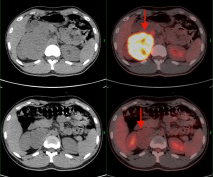

(上两图为:治疗前,下两图为:治疗后)

淋巴瘤治疗前后变化:弥漫性大B细胞淋巴瘤化疗3程后,腹腔机腹膜后多发肿大淋巴结明显缩小,糖代谢明显减低。根据Deauville标准 5PS评分为2分。